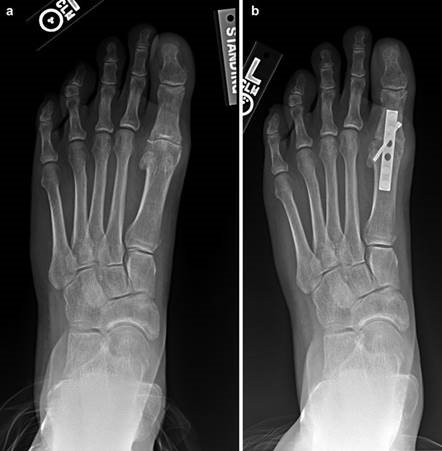

When conservative measures fail, the choice of procedure is dictated by the severity of the deformity, the presence of degenerative joint disease, and the stability of the first TMT joint. Distal osteotomies (e.g., Chevron) are generally reserved for mild to moderate deformities with an intermetatarsal angle (IMA) less than 13 degrees. Diaphyseal osteotomies (e.g., Scarf) offer greater translational correction for moderate to severe deformities. Proximal procedures, such as the Lapidus arthrodesis, are indicated for severe deformities (IMA > 15 degrees), clinical hypermobility of the first TMT joint, or recurrent hallux valgus. For hallux rigidus, joint-sparing procedures like cheilectomy are indicated for early-stage disease, while first MTP arthrodesis remains the gold standard for end-stage arthritis.

Weight-bearing anteroposterior (AP), lateral, and sesamoid axial radiographs are mandatory. On the AP view, the surgeon measures the Hallux Valgus Angle (HVA, normal < 15°), the Intermetatarsal Angle (IMA, normal < 9°), and the Distal Metatarsal Articular Angle (DMAA). The lateral view is scrutinized for Meary's angle (talo-first metatarsal angle) to identify midfoot collapse, as well as the presence of dorsal osteophytes indicative of hallux rigidus. The sesamoid axial view is critical for assessing the degree of sesamoid subluxation and the integrity of the crista.

A V-shaped osteotomy is then created in the metatarsal neck with an apex angle of approximately 60 degrees. The apex is positioned centrally within the metatarsal head, and the limbs exit dorsally and plantarly. The capital fragment is translated laterally by 30-50% of the metatarsal shaft width. If the DMAA is increased, a medial closing wedge can be incorporated into the osteotomy. The osteotomy is provisionally stabilized with a Kirschner wire, and definitive fixation is achieved using one or two headless compression screws directed from dorsal-proximal to plantar-distal. The medial capsule is then imbricated to correct the soft-tissue imbalance, and the skin is closed in layers.

To achieve multiplanar correction, the surgeon must address the sagittal, coronal, and transverse planes. The first metatarsal is plantarflexed to restore the longitudinal arch, rotated out of pronation to realign the sesamoids, and translated laterally to close the IMA. Subchondral drilling or feathering is performed to optimize the biological environment for fusion. Fixation is traditionally achieved with two or three crossed solid or cannulated screws (typically 3.5mm or 4.0mm). Recently, plantar or medial locking plates have gained immense popularity due to their superior biomechanical construct, allowing for earlier weight-bearing. Bone graft or orthobiologics may be packed into the arthrodesis site to stimulate osteogenesis.